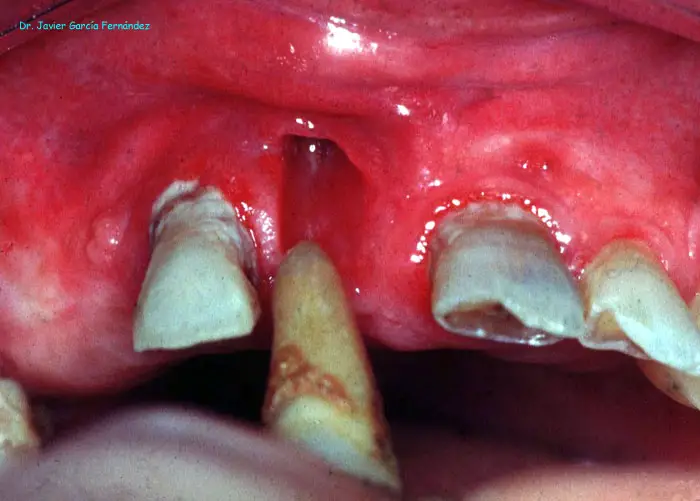

Atlas of Surgical Techniques in Periodontics. Chapter I. Diagnostic of Peridontal Diseases. Classification. Atlas de Técnicas Quirúrgicas en Periodoncia. Cap. I. Exploración y Diagnóstico. Atlas de Técnicas Quirúrgicas en Periodoncia